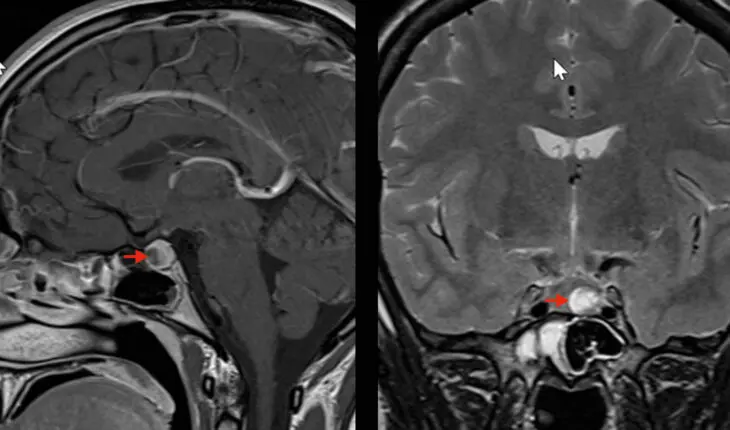

Imagerie d’un adénome hypophysaire